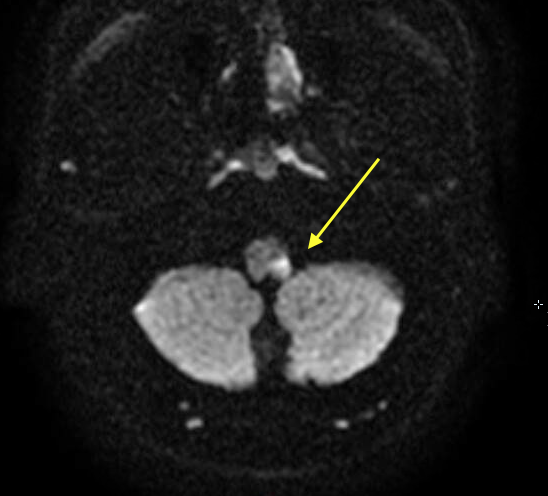

Diagnostic tests. A neurologist was consulted, and magnetic resonance imaging (MRI) of the brain and computed tomography angiography (CTA) of the head and neck were performed to evaluate for carotid artery dissection and for other causes of Horner syndrome. MRI of the brain findings were notable for an acute left lateral medullary infarct (Figure), and CTA showed likely occlusion of the posterior inferior cerebellar artery.

Figure. MRI scan showing an acute infarct in the left lateral portion of the medulla.